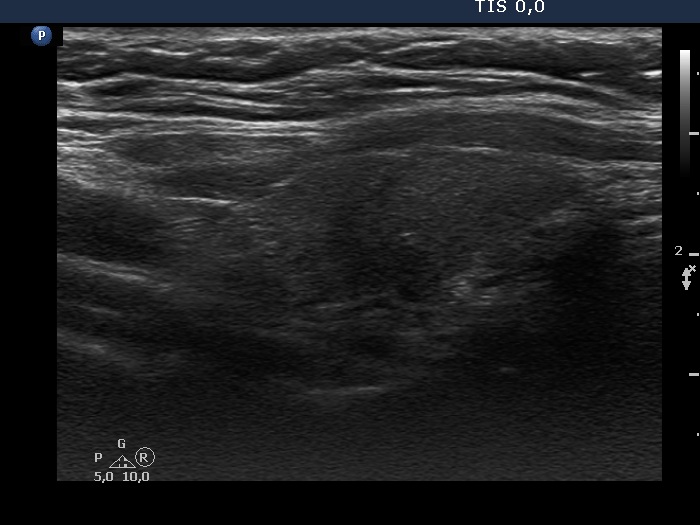

Consecutive patients with the final diagnosis of Hashimoto's thyroiditis - case 30 (246) (ultrasonographic picture 2)

Right lobe, longitudinal scan. There is an irregularly shaped hypoechogenic area in the middle portion of the lobe.